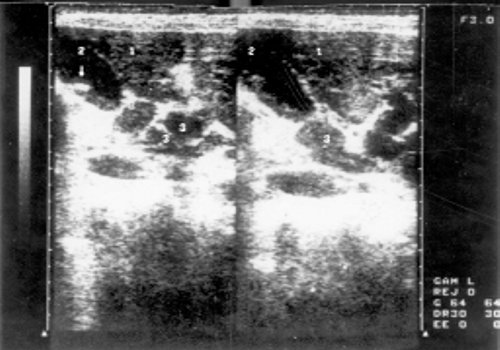

УЗИ лимфоузлов при лимфоме Ходжкина